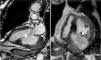

O ecocardiograma transtorácico revelou a presença de pseudoaneurisma/aneurisma ventricular inferior e posterior gigante, preenchido parcialmente por trombo, e condicionando deformação significativa da geometria ventricular (Figura 1; Vídeo 1‐4). Apesar das suas grandes dimensões, o aparelho subvalvular mitral encontrava‐se íntegro, não existindo regurgitação. Dada a dúvida no diagnóstico diferencial, foi realizada ressonância magnética cardíaca que confirmou tratar‐se de aneurisma ventricular gigante (maior eixo de 6,7cm) com trombo no seu interior (Figura 2; Vídeo 5‐6), pelo que iniciou terapêutica anticoagulante. A cintigrafia de perfusão miocárdica exclui isquemia e confirmou necrose do território inferior e posterior. O cateterismo cardíaco pré‐operatório revelou oclusão crónica do segmento proximal da artéria coronária direita e ausência de doença significativa no território coronário esquerdo. A ventriculografia demonstra o volumoso aneurisma ventricular (Figura 3; Vídeo 7). O doente foi submetido a correção cirúrgica do aneurisma: foi observado um volumoso aneurisma da face inferior do ventrículo esquerdo (Figura 4). Após entrada em circulação extracorporal foi feita aneurismectomia parcial com remoção de enorme trombo parietal e encerramento do colo do aneurisma com patch de Dacron® com 2×3cm (Figura 4). O ventrículo esquerdo foi encerrado com sutura contínua. O pós‐operatório decorreu sem intercorrências e o doente teve alta para o domicílio no 5.° dia de pós‐operatório.

Ressonância magnética cardíaca cine‐SSFP: (A) longo eixo, a mostrar aneurisma ventricular gigante (maior eixo 6,7cm)da parede posterior (seta), com trombo no seu interior; (B) curto eixo acima do nível dos músculos papilares, a demonstrar volumoso aneurisma ventricular inferior e posterior (seta), com trombo no seu interior. SSFP: Steady‐State Free Precession.